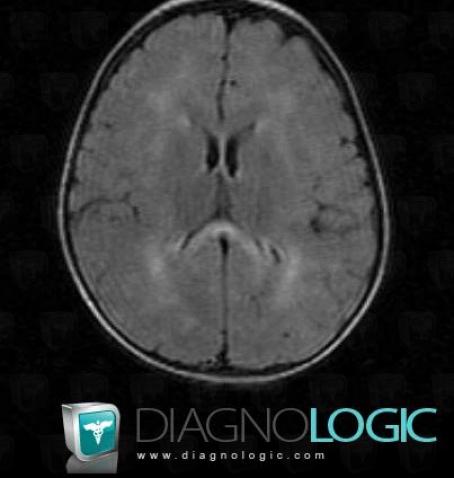

Leucodystrophie métachromatique , Hémisphères cérébraux, Ventricules / Région périventriculaire, IRM

- Diagnostic Leucodystrophie métachromatique , Localisation(s) Hémisphères cérébraux, comportant les gammes Lésions multifocales intracérébrales, Anomalies périventriculaires décelées en IRM, Lésion intracérébrale en hypersignal T2 ou FLAIR, Maladie de la substance blancheVentricules / Région périventriculaire, comportant les gammes Anomalies périventriculaires décelées en IRM